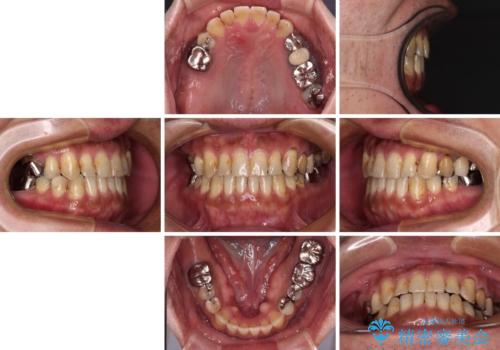

前歯の反対咬合が改善する過程では、奥歯が咬みにくくなるため、食事では辛い思いをされていたようです。

矯正治療後は安定した咬み合わせとなり、顎の違和感がなくなったとのことでした。

今後はむし歯や銀歯を治療していく予定です。